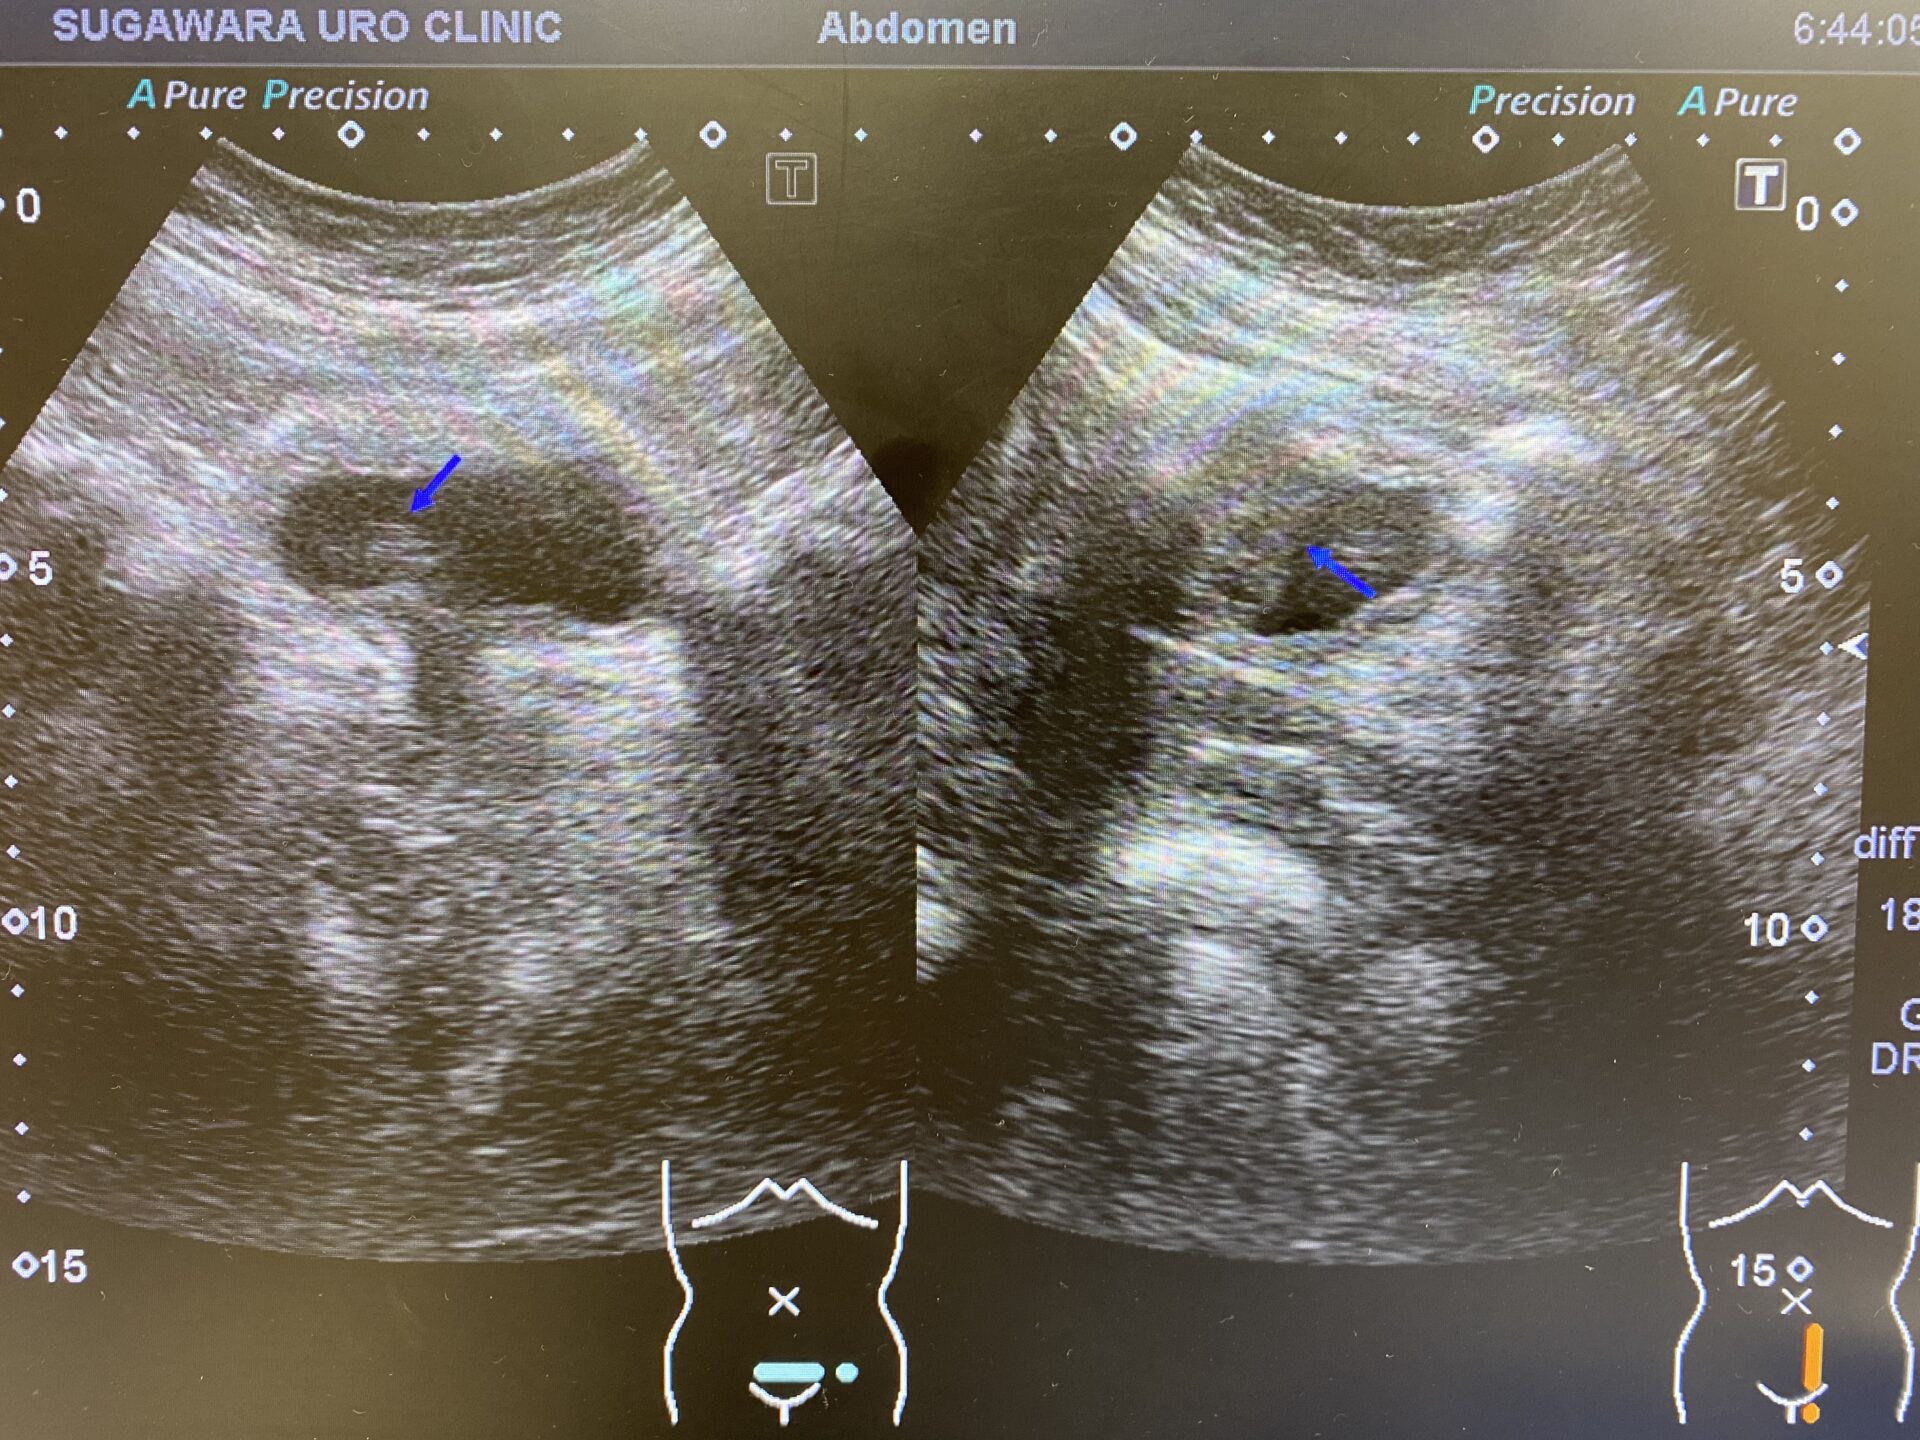

• 超音波。この検査では、高周波音波を使用して体内から画像を作成します。トランスデューサーと呼ばれる装置は、腹部 (経腹超音波) または膣内 (経膣超音波) に設置されます。超音波検査により、子宮内膜症の大きさと位置がわかります。